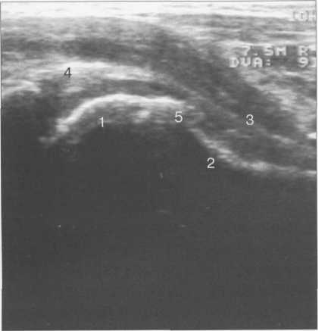

Рис. 19.82. УЗИ тазобедренного сустава по передней поверхности вдоль шейки бедра (8 лет).

1 — головка бедренной кости; 2 — шейка бедренной кости; 3 — капсула сустава и lig. iliofemorale; 4 — хрящевой (фиброзный) лимбус; 5 — зона роста.